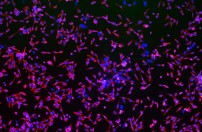

As resistance to antibiotics is becoming increasingly common, it has become even more important to understand the mechanism by which they work on bacterial cells and to develop new antibiotics which can be used agaisnt ’super bugs.’

Fighting resistance to antibiotics